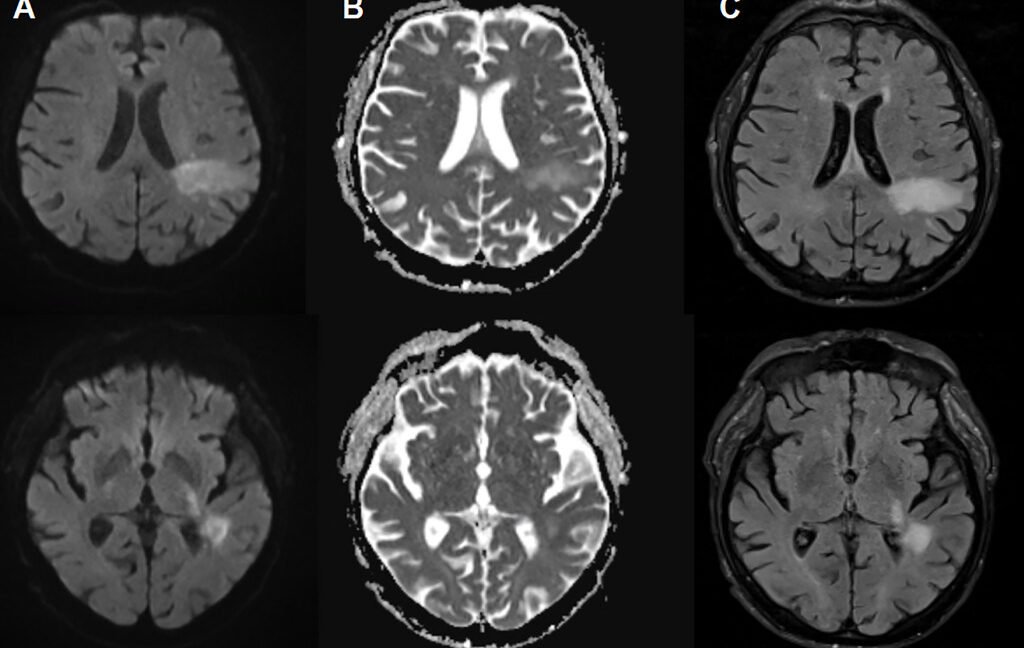

There’s a virus you may have never heard of before that is estimated to infect up to 90 percent of people and lurks quietly in your cells for life—but if it becomes activated, it will destroy your brain. If that’s not startling enough, researchers reported this week that there may be a new way for this virus to activate—one that affects up to 10 percent of adults worldwide.

The virus is the human polyomavirus 2, commonly called either the JC virus or John Cunningham virus, named after the poor patient from whom it was first isolated in 1971. It shows up in the urine and stool of infected people and spreads via the fecal-oral route. Many people are thought to be infected early in life, and blood testing surveys have suggested that 50–90 percent of adults have been exposed at some point.